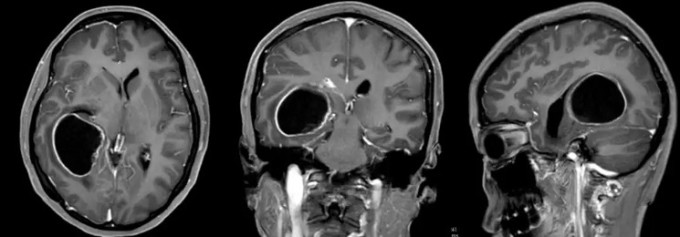

Kết quả chụp chiếu trước phẫu thuật của bệnh nhân Lâm. Ảnh: Ycwb

Bác sĩ Đặng Thiếu Dũng tiếp nhận Lâm trong tình trạng nôn mửa liên tục và lơ mơ. Kết quả MRI xác nhận khối u gây não úng thủy. Êkíp khoa Ngoại thần kinh VII lập tức hội chẩn và quyết định phẫu thuật cắt bỏ khối u. Trưởng khoa Ngô Thái Hoa trực tiếp bóc tách hoàn toàn khối u dọc theo vùng biên tổn thương, đồng thời bảo tồn nguyên vẹn cấu trúc não thất bên. Suốt ca mổ, các bác sĩ dùng hệ thống điện sinh lý thần kinh giám sát liên tục nhằm đảm bảo độ chính xác cao nhất.

Phân tích giải phẫu bệnh sau mổ kết luận Lâm mắc u tế bào thần kinh đệm lan tỏa độ cao (cấp độ 3-4 theo phân loại của Tổ chức Y tế Thế giới - WHO), mang tính ác tính rất cao. Mười ngày sau ca phẫu thuật, người bệnh hồi phục, đi lại bình thường và xuất viện, không mang di chứng. Cô thừa nhận bản thân bỏ qua các triệu chứng đau đầu, chóng mặt dai dẳng từ trước. Người mẹ tự hứa từ nay chấm dứt việc ép con học đến mức vắt kiệt sức lực.